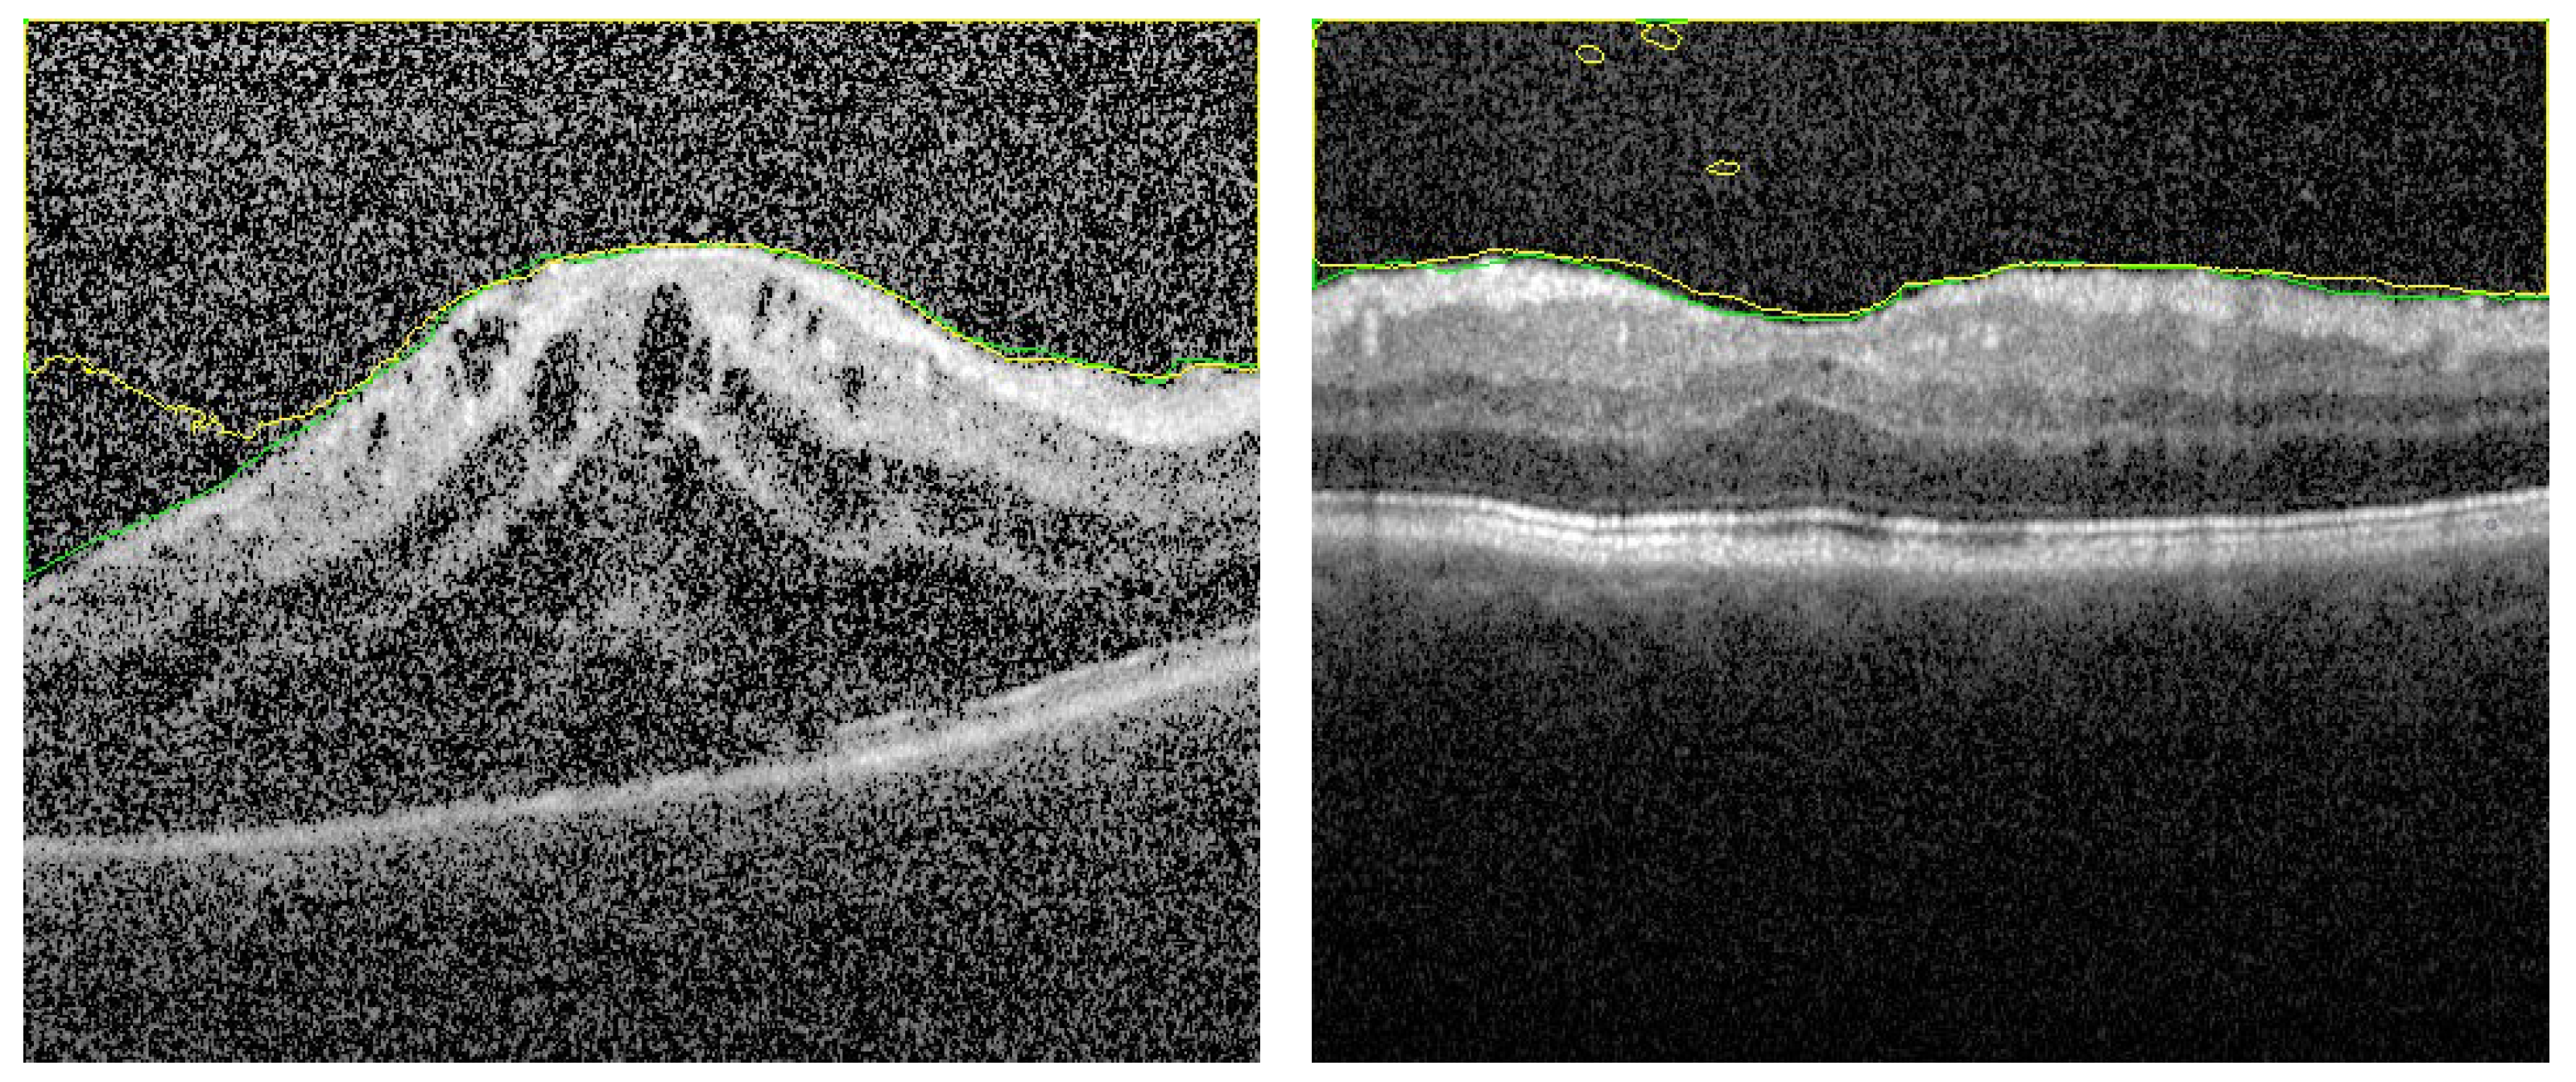

3.2. Fused Image Construction

3.3. Overall Segmentation Evaluation